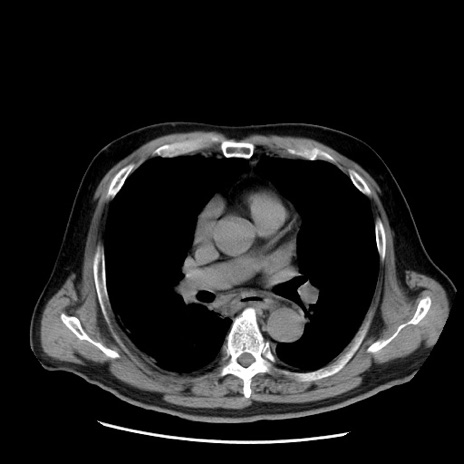

症例20(横断像)

【症例】 60歳代男性

【主訴】 腹部膨満、嘔吐

【現病歴】5日前頃より倦怠感を認め食事量減少し4日前の朝嘔吐、食事摂取困難となった。 3日前近医受診し点滴施行され整腸剤などを処方された。 当日他院を受診し、腹部膨満著明、炎症反応の上昇(CRP10.8、WBC11200)あり、紹介受診となる。

【身体所見】 意識JCS1 受け答えがはっきりしないBP 111/57mHg、 P 67bpm、、BT35.2°C、SpO2 97%(RA)、 腹部:膨隆、打診で鼓音あり、全体的に圧痛有り、腸蠕動音(-)、反跳痛ははっきりせず。

【データ】WBC 11400、CRP 14.20